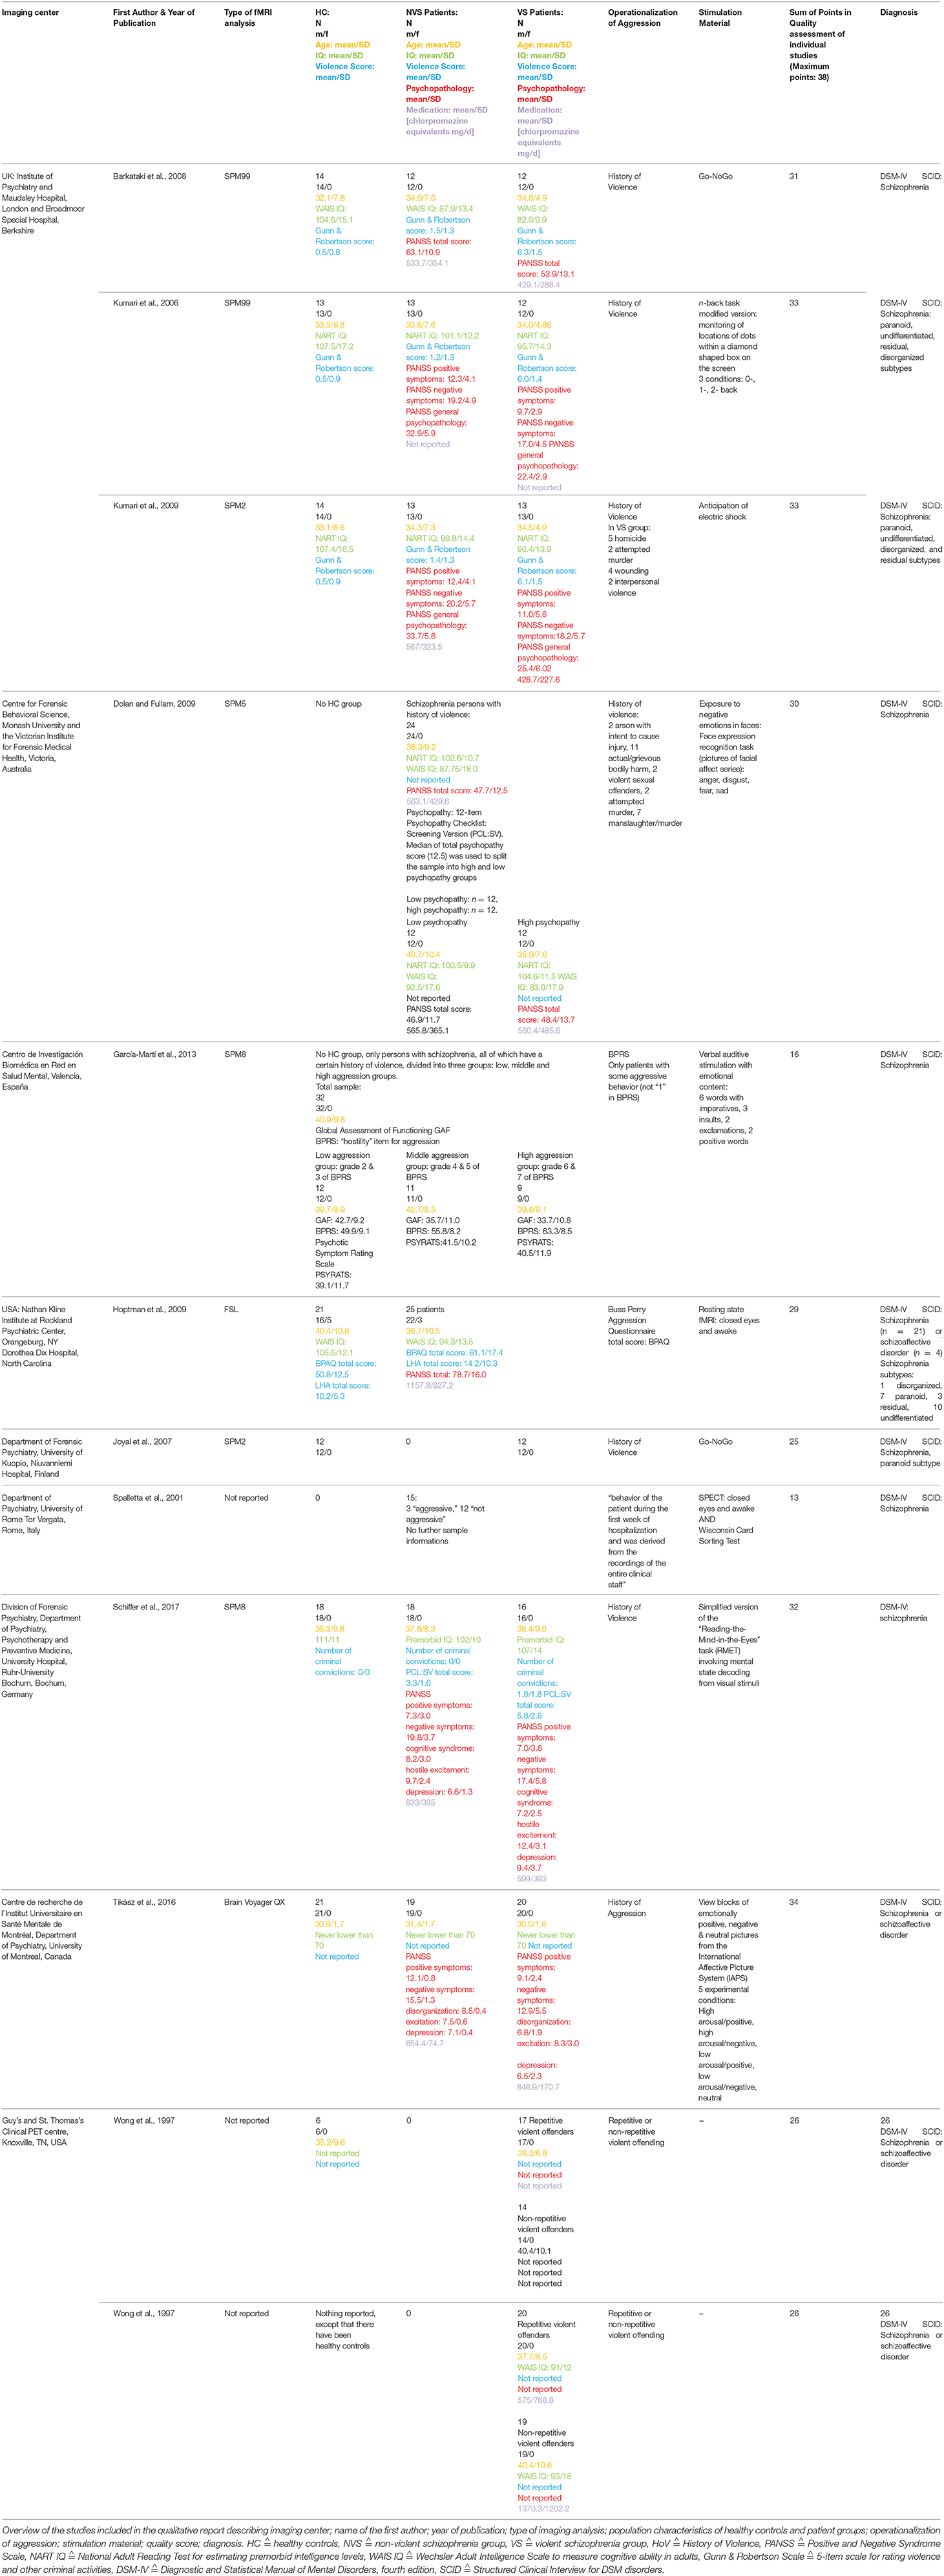

Table 1 gives an overview of all included studies showing imaging center; name of the first author; year of publication; type of functional imaging analysis; population characteristics of HC, and patient groups (group size, gender, age, IQ, violence score, psychopathology, medication); operationalization of aggression; stimulation material; sum of points in quality assessment of individual studies; diagnosis.

Activation Patterns

Table 2 shows fMRI activation patterns across all tasks, brain areas, and group comparisons. For readers interested in more detail in the individual studies, the following sections summarize their results and provide tables about the specific areas and tasks involved. Bearing in mind Table 2, readers can choose to jump directly to the discussion section.